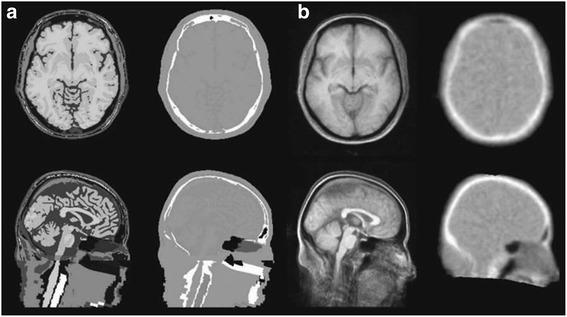

With primitive approaches, the diagnosis and therapy were operated at the cellular, molecular, or even at the genetic level. As the diagnostic techniques are more concentrated towards molecular level, multi modal imaging becomes specifically essential. Multi-modal imaging has extensive applications in clinical as well as in pre-clinical studies. Positron Emission Tomography (PET) has flourished in the field of nuclear medicine, which has motivated it to fuse with Computed Tomography (CT) and Magnetic Resonance Imaging (MRI) for PET/CT and PET/MRI respectively. However, the challenges in PET/CT are due to the inability of simultaneous acquisition and reduced soft tissue contrast, which has led to the development of PET/MRI. Also, MRI offers the better soft tissue contrast over CT. Hence, fusion of PET and MRI results in combining structural information with functional image from PET. Yet, it has many technical challenges due to the interference between the modalities. Also, it must be resolved with various approaches for addressing the shortcomings of each system and improvise on the image quantification system. This review elaborates on the various challenges in the present PET/MRI system and the future directions of the hybrid modality. Also, the different data acquisition and analysis techniques of PET/MRI system are discussed with enhanced details on the software tools.

采用传统方法时,诊断和治疗是在细胞、分子甚至基因层面进行的。随着诊断技术越来越集中于分子层面,多模态成像变得尤为重要。多模态成像在临床以及临床前研究中都有广泛应用。正电子发射断层扫描(PET)在核医学领域蓬勃发展,促使其分别与计算机断层扫描(CT)和磁共振成像(MRI)融合,形成PET/CT和PET/MRI。然而,PET/CT存在一些挑战,比如无法同时采集以及软组织对比度降低,这促使了PET/MRI的发展。此外,MRI比CT具有更好的软组织对比度。因此,PET与MRI融合可将结构信息与PET的功能图像相结合。然而,由于模态之间的干扰,它存在许多技术挑战。此外,必须通过各种方法来解决每个系统的缺点并改进图像量化系统。本综述详细阐述了当前PET/MRI系统面临的各种挑战以及这种混合模态的未来发展方向。同时,还讨论了PET/MRI系统不同的数据采集和分析技术,并对软件工具进行了更详细的介绍。